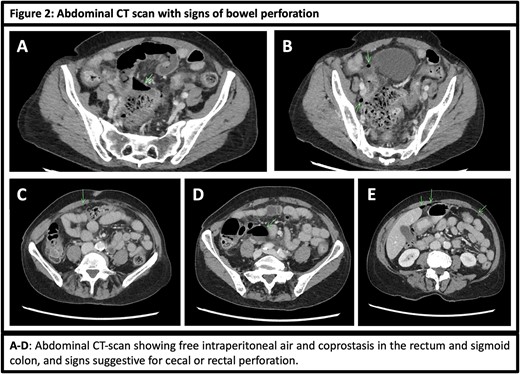

Currently, the patient presents with diffuse, sudden-onset severe abdominal pain along with nausea and vomiting. Clinical examination revealed abdominal tenderness with signs of peritonitis. Laboratory tests showed mild macrocytic anemia (hemoglobin 10.6 g/dl), mild leukocytopenia (white blood cell count: 3310/mcl as a consequence of Palbociclib), and a slightly increased lactate level (2.3 mmol/l). Abdominal X-ray showed no abnormalities (Fig. 1A), but abdominal CT scan revealed signs of bowel perforation, with free intraperitoneal air and fluid in the lower abdomen and pelvis (Figs 1B and C and 2A–E). The sigmoid colon and cecum showed segmentary hypercaptation and bowel wall thickening on abdominal CT scan, suspicious for a bowel perforation at those sites (Fig. 1C).